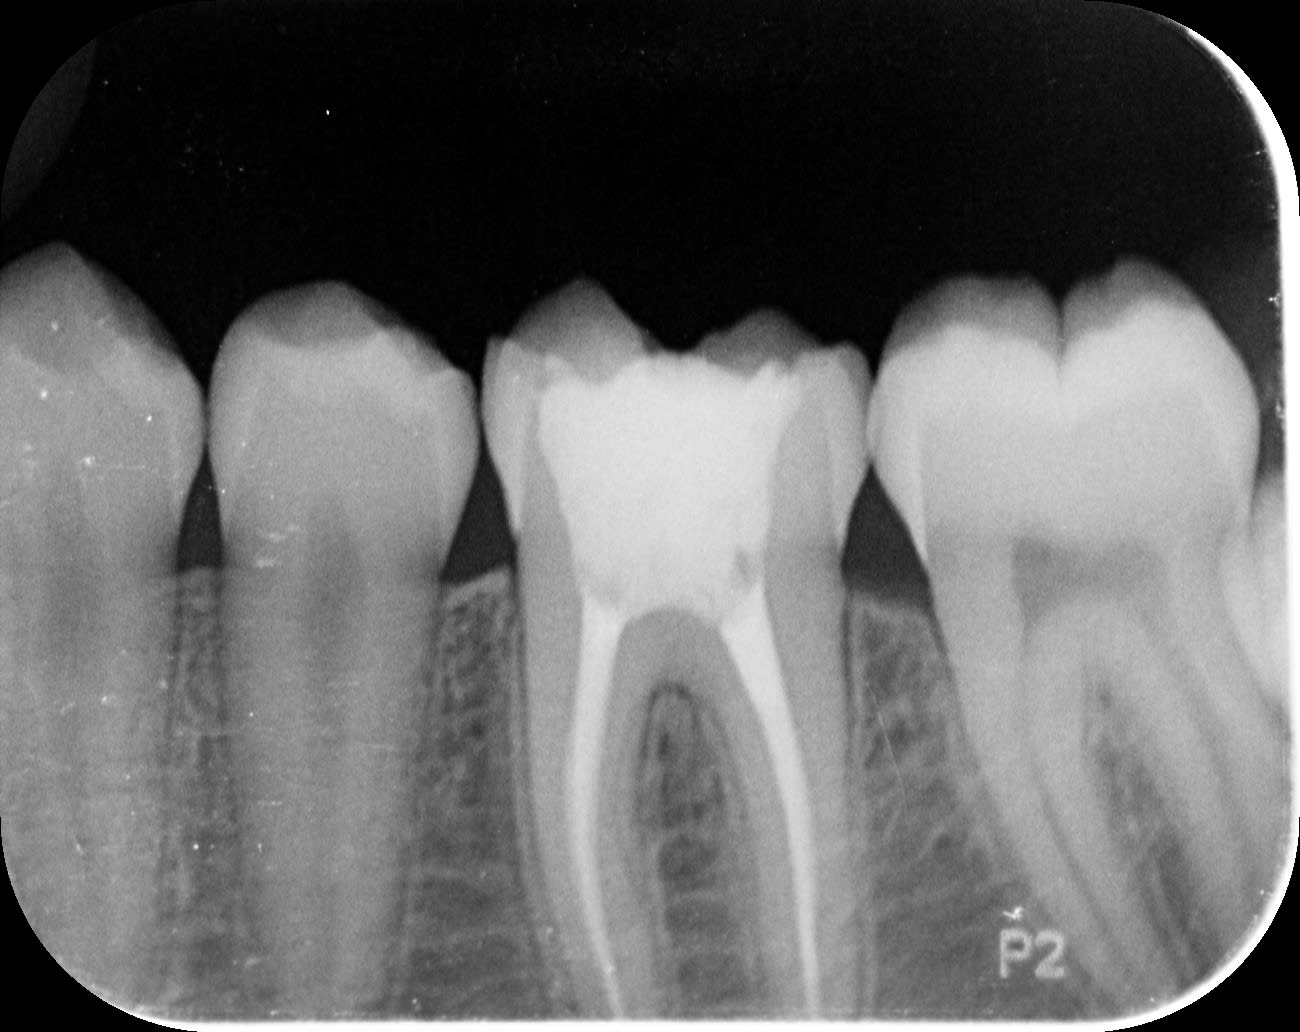

je vous mets en piece jointe la radio 36 37 en 2019 en 1 et 2024 en 2

je lui ai fait endo 36 en 2017 suite grosse carie à 12 ans

en controlant cette dent que l on va couronner bientot si ca va bien,

je remarque une image bizarre dans 37

je pencherais pour resorption interne mais pourquoi et quoi faire? pour l instant je surveille mais sur la radio de 2019 il n y avait pas cette image

Pour moi c’est une résorption externe.

À ta place, je ferais l’endo très rapidement avant une extension vers la racine.

> Pour moi c’est une résorption externe.

> À ta place, je ferais l’endo très rapidement avant une extension vers la racine.

Même chose. Bien vérifier dans le sulcus un point d'entrée.

Tu as confirmé l'image par un autre cliché ( rétrocoronaire)?

Bon je pense que vous avez raison pour la résorption ext mais je n avais rien remarqué

Je vais devoir lui faire endo aussi c est con car a part la 36 le reste nickel... et il a pas trop gardé un bon souvenir de l endo de 36 à 12ans

Ça ne s’envisage pas sans une bonne image 3d pré opératoire. Cette dent est très possiblement condamnée.

+1 il faudrait faire un cbct avant de se lancer dans l’endo à l’aveugle, pour délimiter la lésion et confirmer le diagnostic.

Je peux comprendre l'intérêt du conebeam pour visualiser la lésion.

La rétro est suffisamment claire pour moi. Si la lésion touchait la racine ce serait une autre histoire...

Comme moritooth, ça a beau ressembler salement à une résorption, ne condamne pas la dent sur la base d'une seule radio.

cbct pourquoi pas si délai rapide, autrement je rejoins prunelles, si tu sais de quel coté est la lésion (cherche une coloration rosée à travers l'émail, une petite entrée quelque part), va directement sur le nettoyage de la lésion.

Voir la lésion avant permettra de décider du traitement. Si c’est réellement une résorption externe, l’origine est paro il risque d’y avoir une perte de substance importante sous gingivale sachant qu’il faut éliminer 100% du tissu inflammatoire sinon il y aura récidive. Le traitement endo n’est d’ailleurs pas obligatoire si il n’y a pas de communication avec la pulpe (meme si ca a l’air mal engagé vu la rétro).